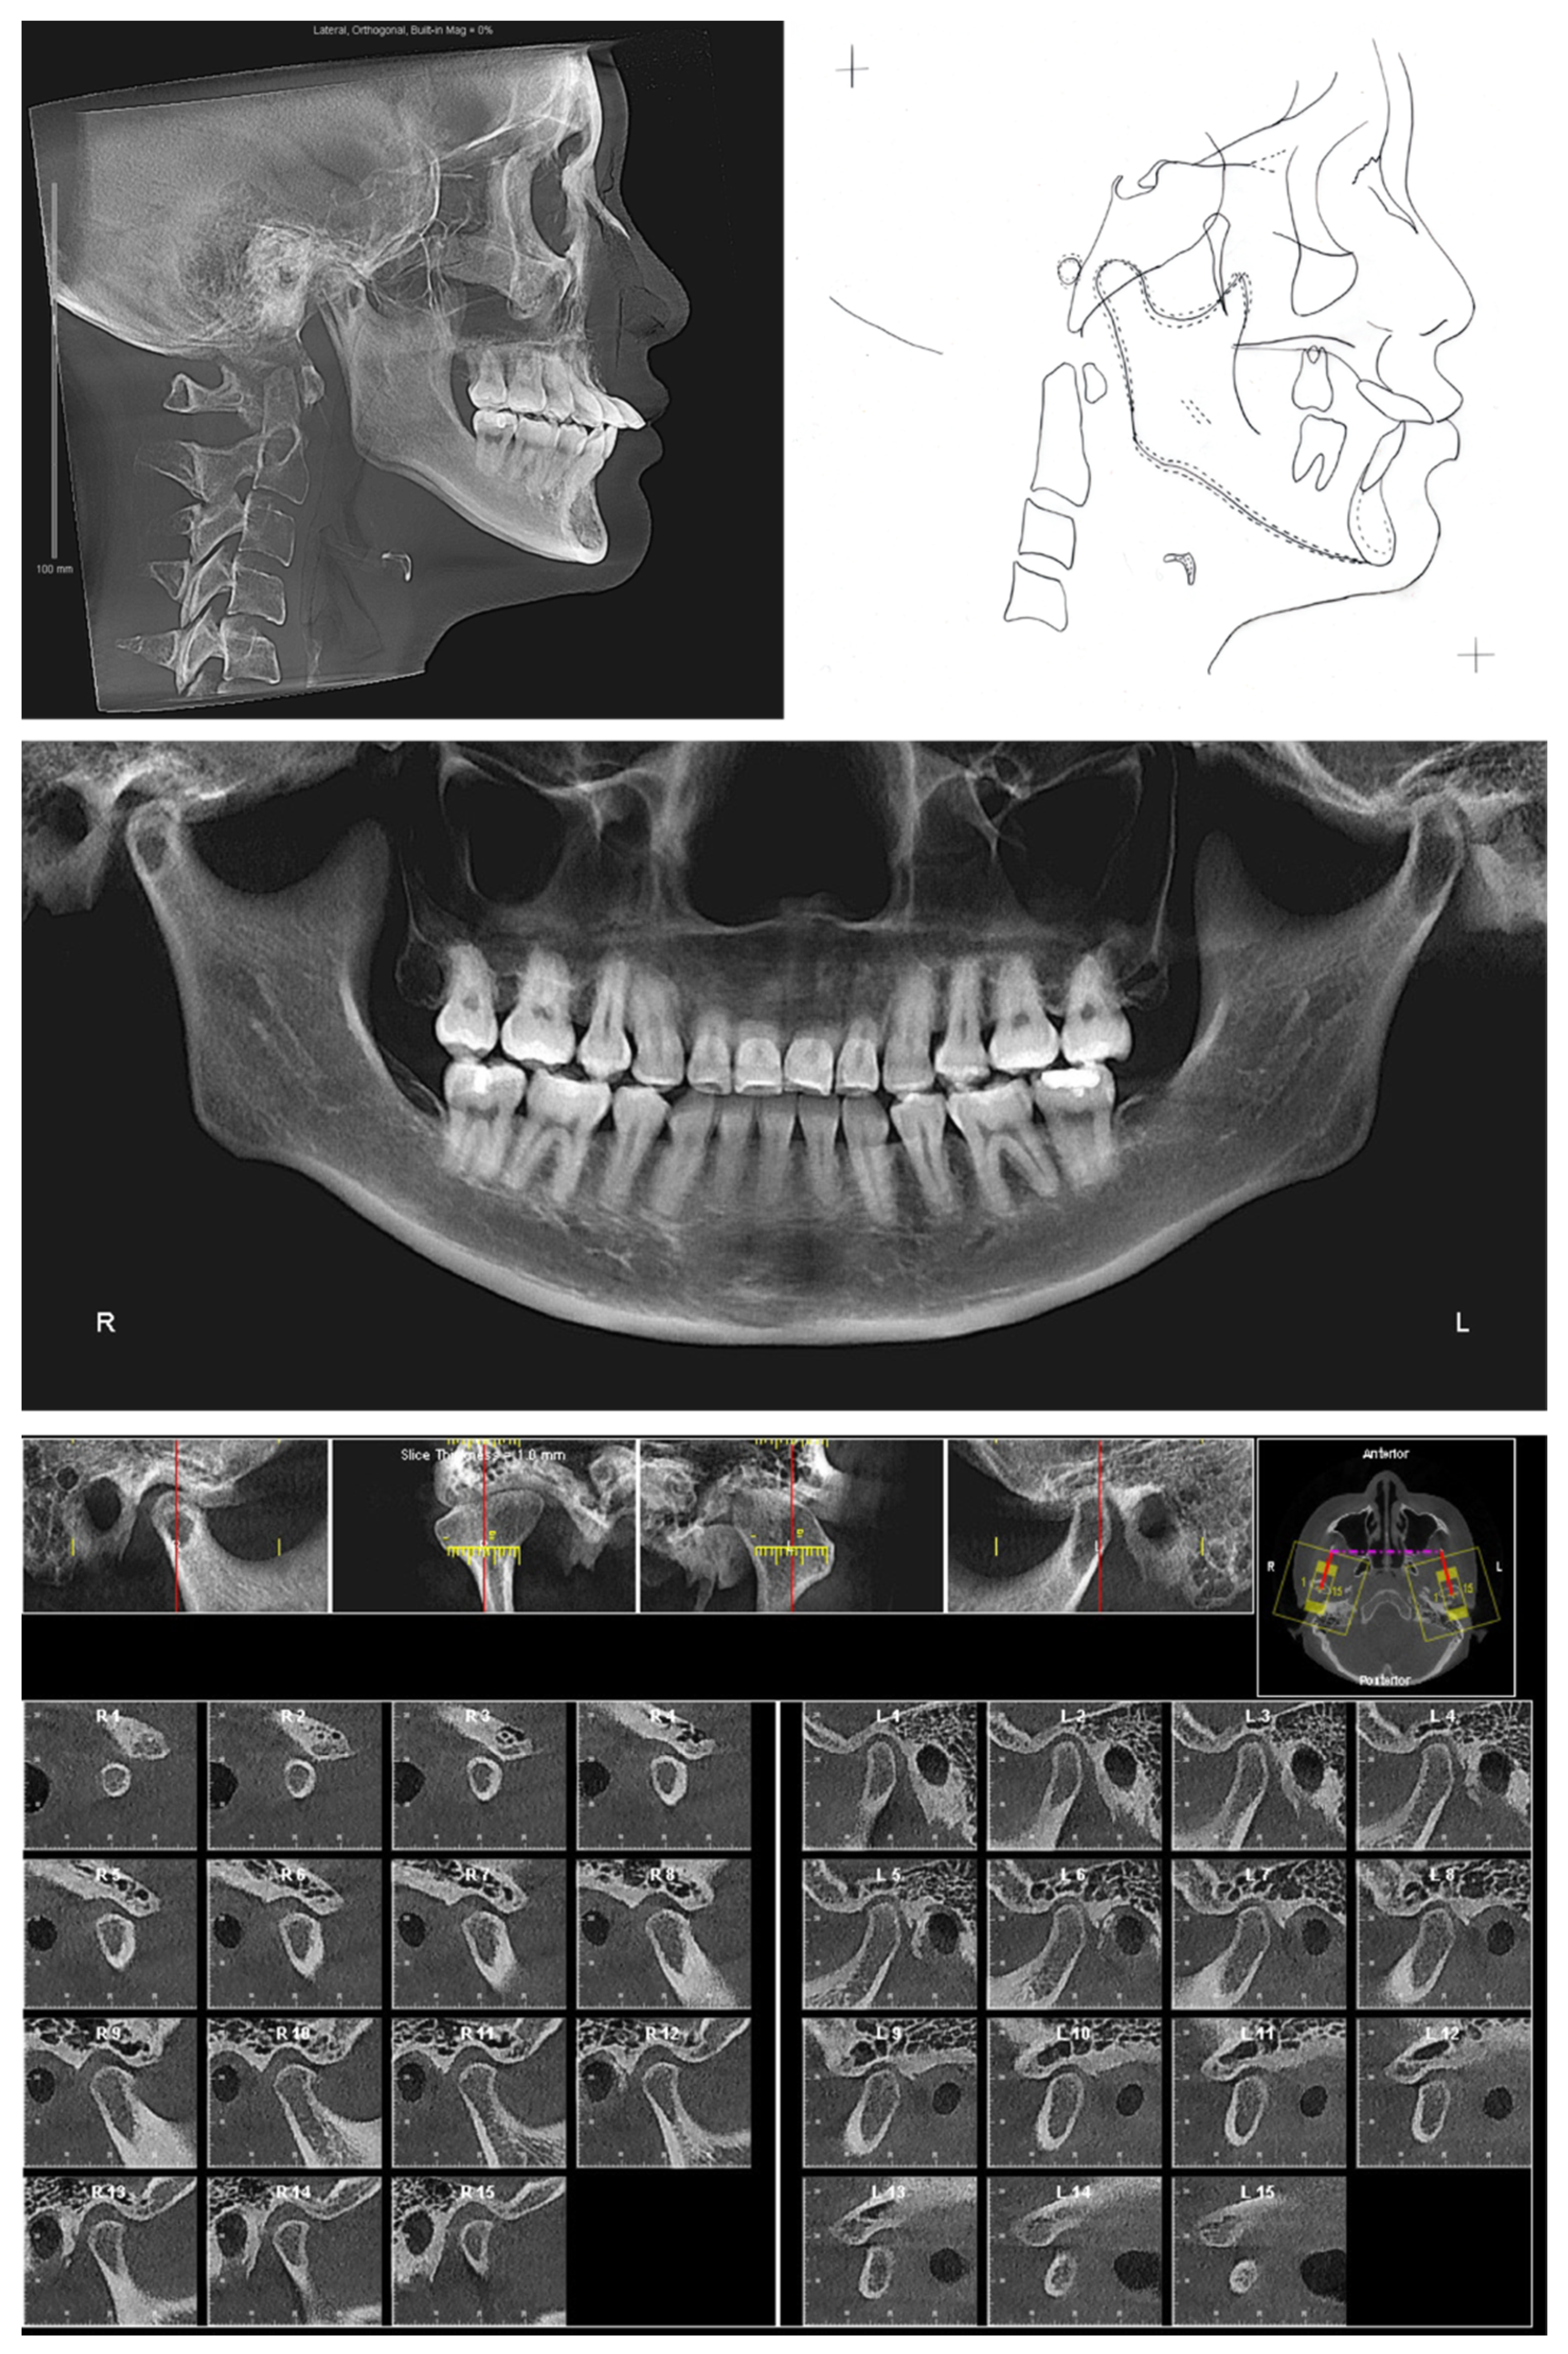

The lateral cephalogram (Figure 2, Table 1) displayed that the patient was skeletal Class III with an orthognathic maxilla. The mandible was in the orthognathic range with prognathic tendency. The patient had a mesofacial skeletal pattern.

The panoramic X-ray (Figure 2) showed that all third molars were missing. Due to the proclination of maxillary anterior teeth, the panoramic X-ray could not properly display the roots of the maxillary anterior teeth. Thus, a series of cross-sections were generated from the CBCT image. As demonstrated in Figure 3 and Table 2, the roots of maxillary incisors were penetrated out of the palatal cortical layer and presented with severe root resorption. The lengths of maxillary canine roots were acceptable, but both canines lacked palatal alveolar bone support.

The clinical exam showed the mouth opening range is within the normal limit. No pain, clicking, or crepitus was detected on either side of the temporomandibular joints. Both joints presented with a well-defined, continuous cortical layer (Figure 2). When comparing the left and right sides, the sagittal slices of temporomandibular joints (Figure 2) showed uneven joint spaces, indicating possible CO-CR discrepancy.

Figure 2. Pretreatment radiographs and cephalometric tracing.